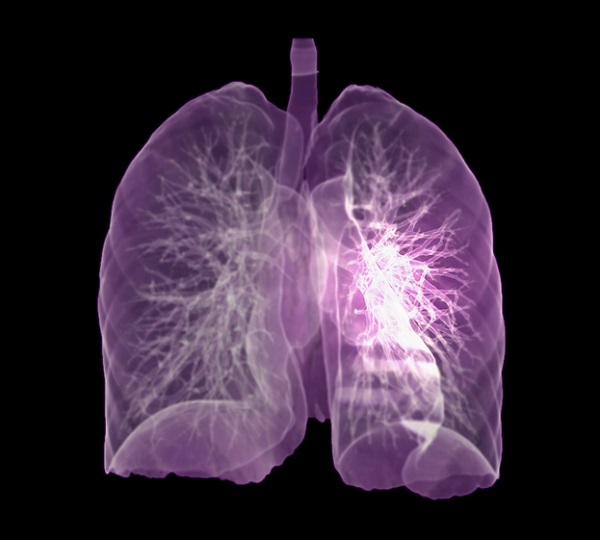

이러한 폐암의 원인으로 인해 폐암으로 진단되기 전에 폐암 초기증상을 조기에 발견하면 다른 장기로의 전이나 진행성 폐암으로의 진행을 어느 정도 지연시키거나 적절하게 치료할 수 있지만 일반적으로 폐암의 초기 단계는 특별한 징후나 증상이 없으므로 조기에 발견하는 경우는 극히 드뭅니다.

폐암 초기증상

잦은 기침

폐암 초기에는 기침이 잦거나 가래가 끓는 등 감기와 같은 증상이 나타날 수 있다. 따라서 폐암은 초기에 암인지 판단하기 어렵다. 또한 객담이나 적혈구를 동시에 토하는 것도 폐암을 진단하는 가장 중요한 증상 중 하나이다. 붉은 피가 섞인 가래 증상이 있으면 병원에 가서 검사를 받아야 한다.

또는 가래, 기침, 목소리가 쉬지 못하는 등 가벼운 감기라고 생각하여 폐암이 진행된 후에 종양이 발견되는 경우가 많습니다. 폐렴은 또한 기관지의 감염성 종양을 동반할 수 있습니다. 또한, 그럼에도 불구하고 폐렴만을 중심으로 치료를 하다 보면 상세한 검사 결과로 인해 종양을 식별하지 못하거나 폐암으로 발전할 수 있습니다.